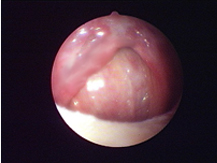

經(jīng)典案例

手術(shù)圖片